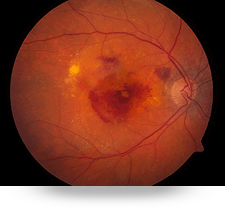

La degeneración macular asociada a la edad es una enfermedad que afecta la visión central, el daño es en la macula. Las personas refieren disminución de la agudeza visual con incapacidad de realizar actividades cotidianas como conducir o leer. Se presenta generalmente en personas mayores de 65 años, en donde se forma una membrana con vasos sanguíneos por debajo de la macula.